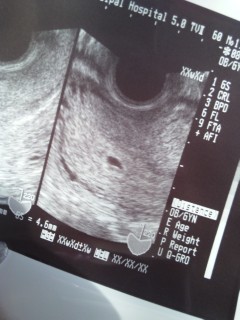

生理予定日から6日後に病院へ行き、確認してもらいました。

先生から、エコーで見ながら「ちゃんと子宮内にいますね。」と言っていただき、検査台に乗ったままの状態で思わず「よかったー!」と言ってしまいました^^;

生理予定日に検査薬で陽性反応が出ていましたが、 その3日後あたりから左下腹部一点がズキズキ痛みがあったため、子宮外妊娠が心配でしたが、無事正常妊娠でした。